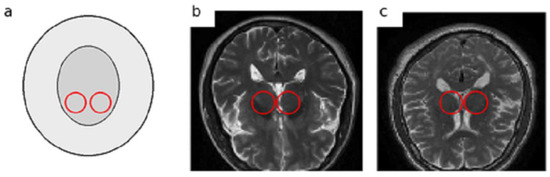

In the early stages of PD, non-motor symptoms overlap with other neurological diseases like Multiple System Atrophy (MSA) or drug-induced Parkinsonism, the clinical diagnosis faces serious challenges [6,7]. These non-motor symptoms, including sleep disturbances, depression, olfactory dysfunction, and subtle cognitive changes, are often nonspecific and can lead to misdiagnosis or delayed diagnosis even by experienced clinicians [8]. MRI plays a vital role in assessing and monitoring structural and functional changes in the brain. It offers a non-invasive, safe, and cost-effective technique. T2-weighted MRI images, owing to their high contrast between grey and white matter and sensitivity to tissue changes, allow clear visualization of subcortical structures such as the SN and basal ganglia. These characteristics make T2-weighted MRI particularly suitable and widely employed in studies of PD [9]. Despite the potential of MRI for detecting structural brain changes, reliably identifying subtle nigral alterations in early-stage Parkinson’s disease remains highly challenging. Manual or semi-quantitative MRI assessments are prone to considerable diagnostic errors, reported to be ≥25. Furthermore, subtle structural changes in the substantia nigra and basal ganglia are often difficult to distinguish from normal ageing, resulting in significant inter-observer variability. These limitations highlight the need for automated, objective, and reproducible approaches capable of detecting fine-grained nigral changes that often escape human visual perception [10]. To better illustrate the anatomical target and the nature of T2-weighted structural MRI (sMRI) data used in this study, we provide representative examples with the approximate SN region highlighted Figure 1. Note that on conventional T2-weighted images, nigral alterations associated with early PD can be subtle and reader-dependent, motivating automated feature learning approaches.

Figure 1.

Representative T2-weighted sMRI examples with approximate SN localization: (a) schematic depiction of the substantia nigra (SN) region, (b) PD patient, and (c) healthy control. Highlighted circles indicate the approximate SN region.